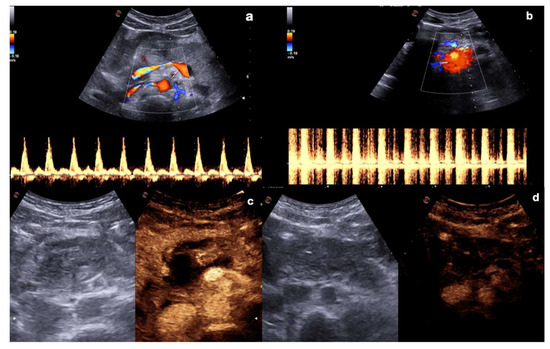

The administration of the UCA should be preceded by a preliminary study with a color and power Doppler US (CD–US) of the injured parenchyma to identify any contained vascular lesions. This increases the diagnostic confidence in differentiating these lesions through their characteristic spectral pulsed-wave Doppler (Figure 2).

Figure 2.

Role of color and spectral Doppler in the detection of post-traumatic vascular complications. Color (upper row) and spectral (bottom row) Doppler of the right kidney show post-traumatic pseudo-aneurysm in a 20−year-old man admitted to the emergency department for hematuria two weeks after a car accident and previous CT diagnosis of traumatic right kidney contusion (a); color Doppler shows turbulent flow in the false aneurysm, whereas spectral Doppler shows a “to and fro” spectrum. Color (upper row) and spectral (bottom row) Doppler of left kidney show post-traumatic arteriovenous fistula in a 45−year-old woman admitted at emergency department for penetrating injury (b); color Doppler shows aliasing artifact due to the presence of a focus of increased blood flow, then confirmed at pulsed Doppler that shows high-velocity peak without a clear diastolic flow.

Indeed, after UCA administration, these lesions could become indeterminate at CD–US evaluation due to the relative turbulence generated by the micro-bubbles; furthermore, the relative destruction of the micro-bubbles due to high MI during the Doppler study may also render the contrast study ineffective (Figure 3).

Figure 3.

Artifacts in color and spectral Doppler after CEUS (a,b), and in repeated CEUS after Doppler (c,d). Mesenteric artery color and spectral Doppler before (a) and after (b) UCA administration showed alteration in the color map (upper row) as well as in the waveform (bottom row) evaluation due to the relative turbulence generated by the micro-bubbles within the vessel. Upper abdomen CEUS in pancreatic trauma before (c) and after (d) Doppler study shows relative destruction of the micro-bubbles due to high MI during the Doppler study, making the post-Doppler contrast study unable to visualize organs and tissues properly.